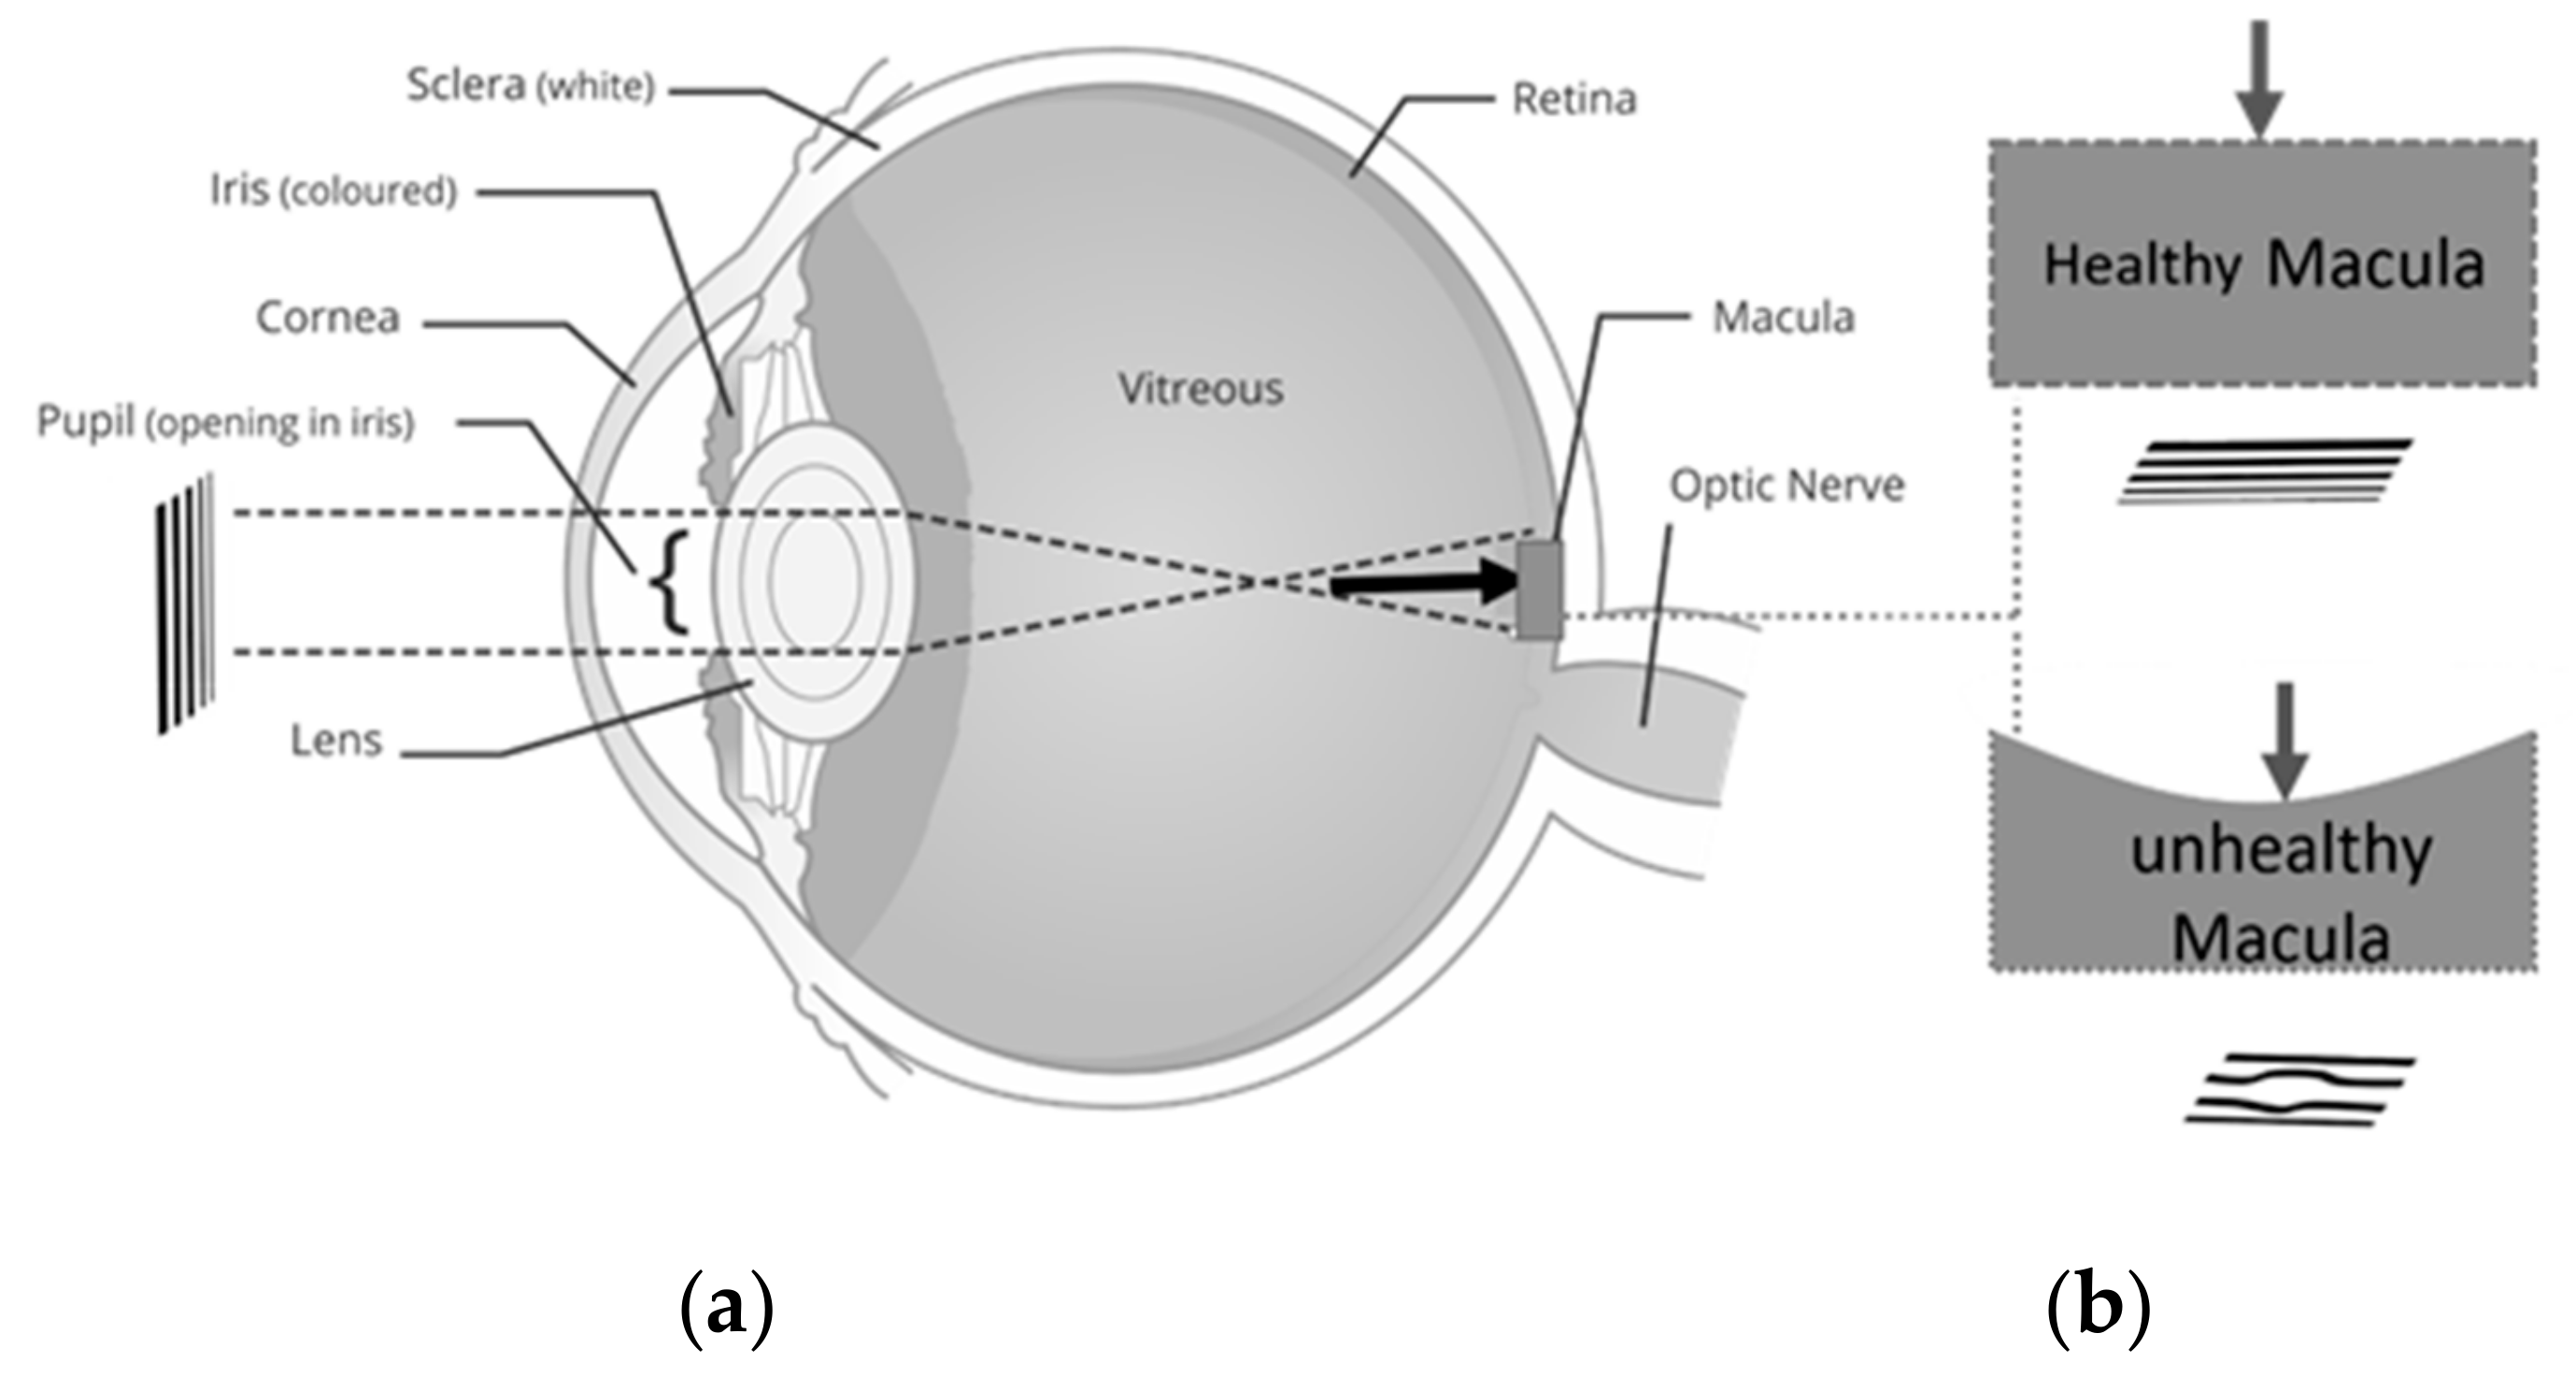

3. CSR VD Changes

3.1. Effect of CSR in the Visual Field